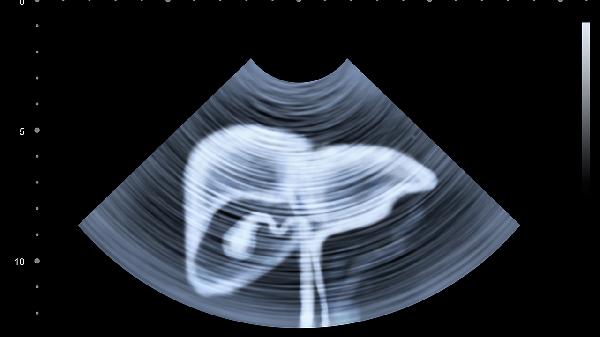

膽紅素代謝障礙會(huì)引起皮膚、鞏膜黃染,尿液呈濃茶色,糞便顏色變淺。急性黃疸多見(jiàn)于甲型肝炎或膽管梗阻,慢性黃疸可能與原發(fā)性膽汁性膽管炎有關(guān)。需檢測(cè)總膽紅素和直接膽紅素比值,必要時(shí)進(jìn)行腹部超聲。藥物治療可選用熊去氧膽酸膠囊、腺苷蛋氨酸腸溶片。

建議保持規(guī)律作息,避免熬夜和飲酒。飲食選擇易消化的優(yōu)質(zhì)蛋白如魚(yú)肉、豆腐,控制動(dòng)物內(nèi)臟攝入。定期監(jiān)測(cè)肝功能指標(biāo),出現(xiàn)蜘蛛痣、肝掌等體征時(shí)及時(shí)就醫(yī)。肝硬化患者需每6個(gè)月進(jìn)行甲胎蛋白和肝臟超聲篩查。注意個(gè)人衛(wèi)生,接種乙肝疫苗可有效預(yù)防病毒性肝炎。